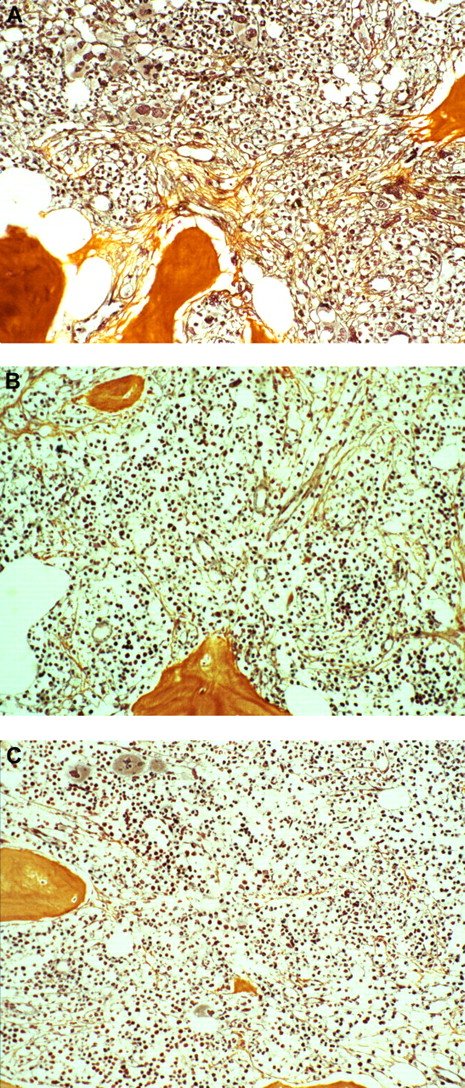

In a subset of patients (n = 16) treated in one center (Hamburg), a sequential analysis of bone marrow fibrosis regression was performed after engraftment (between day 30 and day 50), on day 100 and day 365 after transplantation by 2 hemato-pathologists (J.T., H.M.K.). Before transplantation, all patients had advanced grade 2 (n = 5) or grade 3 (n = 11) bone marrow fibrosis. Shortly after engraftment, 21% had a regression from grade 3 to 2 and 36% had near or complete resolution (grade 1 or 0) of bone marrow fibrosis. A near or complete resolution (grade 1 and 0) at day 100 and day 365 was observed in 69% and 93%, respectively (Figure 2).

Representative fibrosis regression after dose-reduced allograft. Bone marrow fibrosis grade 3 before transplantation (A), grade 1 after engraftment on day 30 (B), and grade 0 on day 100 after allogeneic stem cell transplantation (C). Image acquisition specifications: Zeiss Axioplan microscope; magnification ×180, oil; Plan Apochromat 20×/0.60 imaging medium/solution; Axiocam HRC camera; Adobe Photoshop software.